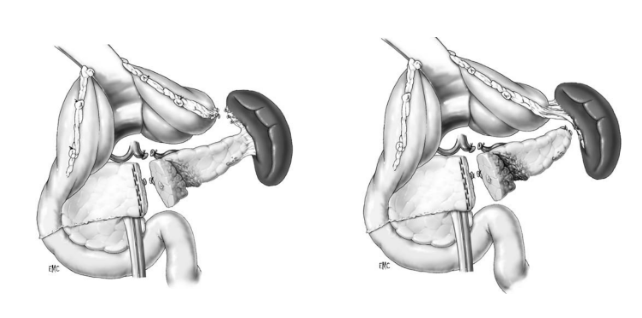

Phẫu thuật bảo tồn chấn thương tá tràng

- Tụ máu thanh mạc, tụ máu dưới niêm mạc, rách thanh cơ chưa thủng: - Khâu thanh mạc, lấy máu tụ

- Rách thủng thành tá tràng:- Khâu đơn thuần: tổn thương nhỏ, đến sớm

- Mở thông giảm áp: Kehr (Stone 1979), 3 ống thông (Hasson 1984)

- Túi thừa hoá tá tràng (Berne 1974)

- Loại trừ môn vị (Jordan 1977)

- Nối quai ruột vào vết thương (Patch)

A – Thương tổn độ I ở đầu tụy, độ III (AAST) ở D2

B – Khâu vết thương tá tràng D2, mở thông túi mật, mở thông dạ dày, mở thông hỗng tràng, dẫn lưu HCMN và cạnh tá tràng (theo C.Arvieux, C.Létoublon 2005)

Phẫu thuật loại trừ môn vị – Pyloric exclusion procedure

Vỡ tá tràng, vỡ tuỵ không tổn thương ống tụy chính được điều trị bằng khâu tá tràng, khâu tuỵ, mở thông tá tràng qua Kehr, khâu môn vị, nối vị tràng, hút dạ dày qua dẫn lưu (theo Kenneth D. Boffard và Adam J.Brooks – 2000)